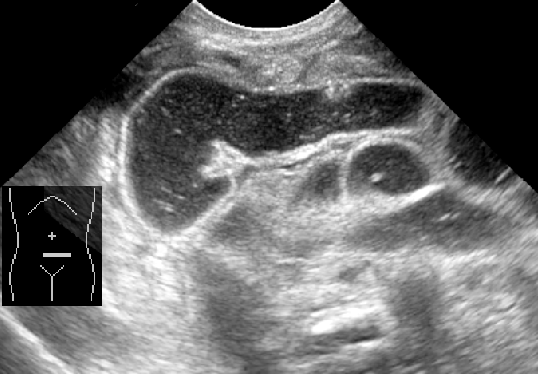

Caracterizada por un engrosamiento anormal del músculo pilórico, lo que lleva a una obstrucción de la salida gástrica. Esta condición es una causa común de vómitos no biliosos en lactantes y generalmente se presenta entre las 2 y 12 semanas de vida.

El diagnóstico se realiza principalmente mediante ecografía, que muestra un alargamiento constante y un engrosamiento de la pared del píloro, con una longitud del canal pilórico superior a 18 mm y un grosor muscular de al menos 4 mm.

Ejemplos de estenosis pilorica hipertrofica infantil.